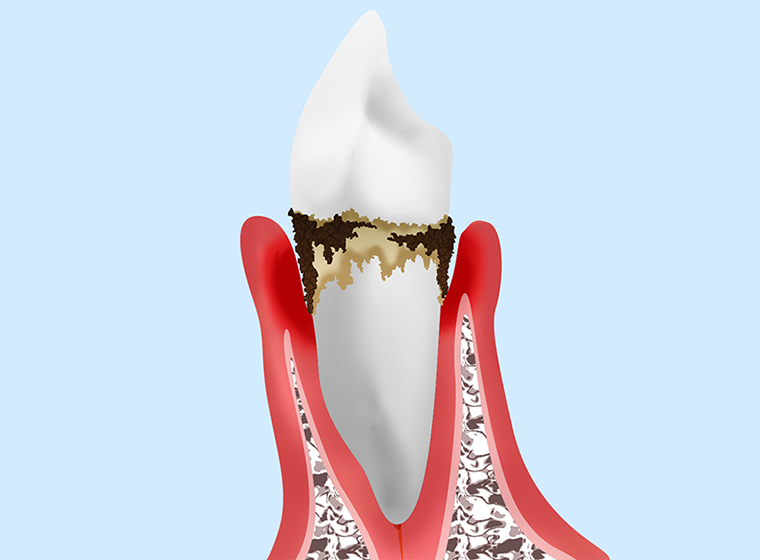

歯周病の進行段階

初期段階

|

「歯肉炎」と呼ばれる状態です。歯ぐきが炎症を起こしており、歯周ポケットの深さは4mm以内です。歯肉が赤く腫れ、ブラッシングの際に出血することがあります。 |

第2段階

|

歯を支える顎の骨にまで炎症がおよんだ状態で、「軽度歯周炎」から「中度周囲炎」の状態です。歯周ポケットの深さは4~6mmです。口臭が強くなり始め、歯がぐらつきだします。 |